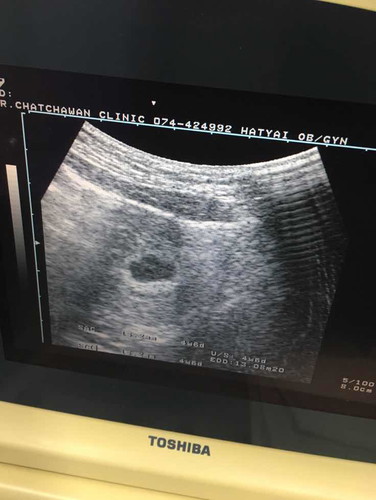

คุณหมอบอกว่าอยู่ตำแหน่งที่ดีไม่มีโอกาสแท้งให้ยาบำรุงมาทาน แต่วันนี้เป็นแบบนี้ค่ะ

มีเลือดออก!! ไปหาหมอยังคะ รีบไปพบหมอดีกว่าคะ